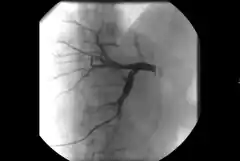

Cyfrowa angiografia subtrakcyjna (ang. DSA, Digital Subtraction Angiography) – badanie diagnostyczne przedstawiające dokładny przebieg naczyń krwionośnych w tkance kostnej i tkankach miękkich. Można obrazować także inne struktury anatomiczne, np. drogi żółciowe. Podczas badania rejestrowane są dwa obrazy rentgenowskie, przed podaniem kontrastu zwany „maską" i po podaniu kontrastu jeden po drugim. Są one elektronicznie zapisywane w formie cyfrowej, w tym jeden w postaci negatywu. Odjęcie (subtrakcja) obrazu „maski" od obrazu z kontrastem powoduje, że wszystkie dodatkowe detale znikną tworząc jednolity, szary obraz. Jednak jeśli między dwiema ekspozycjami wystąpią różnice w zawartych elementach obrazów, np. wstrzyknie się do krwiobiegu określoną ilość środka cieniującego, jedyną rzecz, którą będzie można zobaczyć, to kontrast widoczny w naczyniach krwionośnych. Wszystkie inne szczegóły bez cieni z nakładających się tkanek, w tym także kości zacierające obraz, pozostaną szare. Zapewnia to wyraźny obraz naczyń i pozwala na zastosowanie niższej dawki środka kontrastowego[1][2][3].

Cyfrowa angiografia subtrakcyjna służy do tworzenia obrazów naczyń krwionośnych bez zakłócających cieni z nakładających się tkanek. Aby to uzyskać obraz bez kontrastu (obraz maski) obszaru badanego jest wykonywany przed wstrzyknięciem środka cieniującego i pokazuje anatomię, a także wszelkie nieprzepuszczalne dla promieni rentgenowskich ciała obce (klipsy chirurgiczne, stenty itp.), podobnie jak zwykły obraz rentgenowski. Obrazy kontrastowe wykonywane kolejno podczas wstrzykiwania materiału kontrastowego przedstawiają wypełnione kontrastem naczynia z uwzględnieniem upływu czasu nałożone na inne tkanki i są przechowywane w komputerze. Obraz maski jest następnie odejmowany od obrazów kontrastowych piksel po pikselu. Końcowe obrazy odejmowania pokazują tylko wypełnione środkiem cieniującym naczynia. Rejestracja może kontynuować sekwencję odejmowanych obrazów w oparciu o początkową maskę. Obrazy odejmowania można oglądać w czasie rzeczywistym. Nawet jeśli pacjent leży nieruchomo, z pewnością wystąpi pewien stopień błędnej rejestracji obrazów z powodu ruchu między pozyskaniem obrazu maski a kolejnymi obrazami kontrastowymi. Przesunięcie pikseli (ręczne lub automatyczne), tj. retrospektywne przesunięcie maski, może zminimalizować błędną rejestrację, ale ruchy ogniskowe, takie jak perystaltyka jelit, nie zostaną skorygowane[1][2][3].